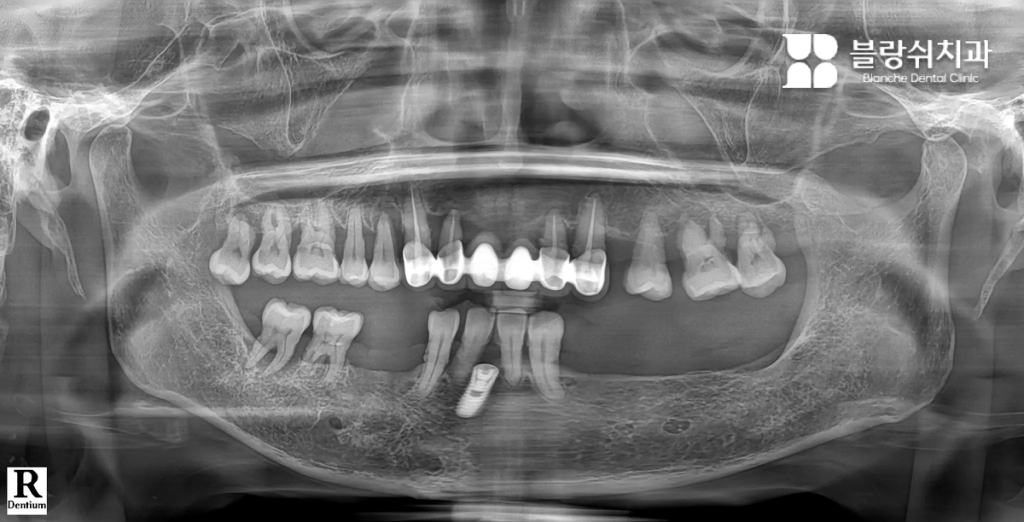

Case 1. 틀니와 장기 치료가 부담이었던 50대 남성

이 환자분은 여러 개의 치아 손상과 잇몸 약화로 인해 정상적인 저작이 어려운 상태였습니다. 전통적인 전체 임플란트를 고려했지만, 수개월에서 1년 이상 소요되는 치료 기간과 잇몸 절개 수술에 대한 부담으로 치료를 망설이고 계셨습니다. 특히 “잇몸을 크게 절개해야 한다”는 점이 가장 큰 두려움이었습니다.

- 디지털 풀아치 임플란트를 선택한 이유 인터넷 검색을 통해 디지털 풀아치 임플란트를 알게 되었고, 짧은 치료 기간과 최소 절개 수술이라는 점에 관심을 갖고 내원하셨습니다. 상담 과정에서 3D CT와 디지털 스캐닝을 통해 구강 상태를 정밀 분석했고, 임플란트 개수를 최소화하면서도 전체 치아 기능을 회복할 수 있는 구조라는 설명을 듣고 치료를 결정하셨습니다.

- 치료 후 변화 “이제는 음식 종류를 가리지 않고 먹을 수 있어서 삶의 만족도가 확실히 달라졌습니다.” 디지털 스캔 데이터를 기반으로 3D 치료 계획을 수립한 뒤, 컴퓨터 가이드 수술로 임플란트를 정확한 위치에 식립했습니다. 이후 CAD/CAM 기술로 제작된 풀아치 보철물을 장착하며 치료가 진행되었고, 적은 방문 횟수로 치료를 마칠 수 있었습니다.